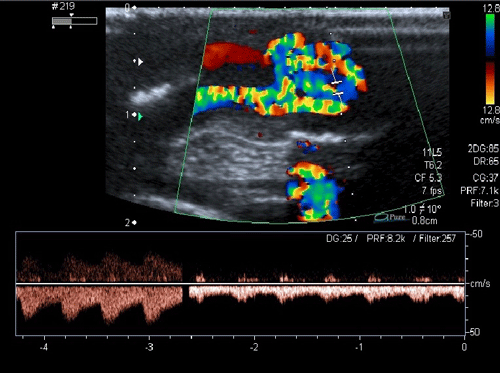

Figure 3: Umbilical arteries arising from both internal iliac arteries, flowing into the mass directly at the end of the umbilical cord.  |

A 20-day-old male neonate with an umbilical hernia was referred to our hospital because of persistent wet umbilicus. Umbilical examination showed a 2 cm diameter umbilical hernia and a long epithelialized pulsatile cord with granulomatous tissue at its end (Fig. 1). Palpable thrill was note at the midportion of the umbilical cord. Doppler ultrasonography revealed a mass at the end of the umbilical cord harboring dilated blood vessels with turbulent blood flow (Fig. 2). This vascular mass continued to the umbilical vein, which was dilated and flowed into the liver. Abdominal contrast-enhanced computed tomography revealed umbilical AVM; the umbilical arteries were patent from both internal iliac arteries, flowed into the mass directly at the end of the umbilical cord, and the dilated umbilical vein flowed out from the mass, continuing from the umbilicus to the umbilical part of the portal vein in the liver (Fig. 3, 4).